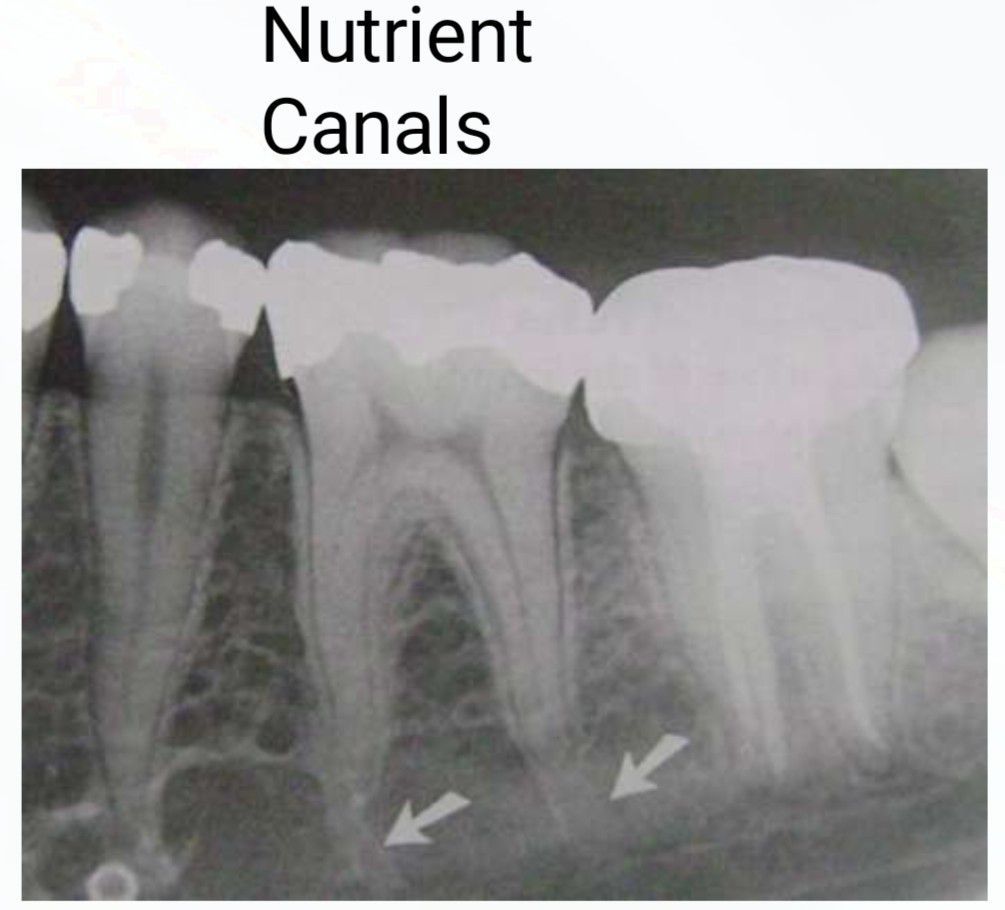

Nutrient Canals

This is how nutrient canals looks in an intraoral radiograph.